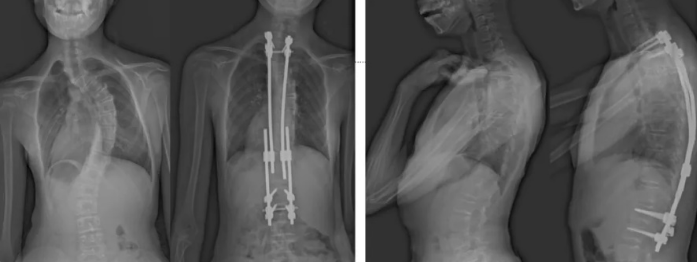

白玛的正位术前、术后对比图(左侧);侧位术前、术后对比图(右侧)